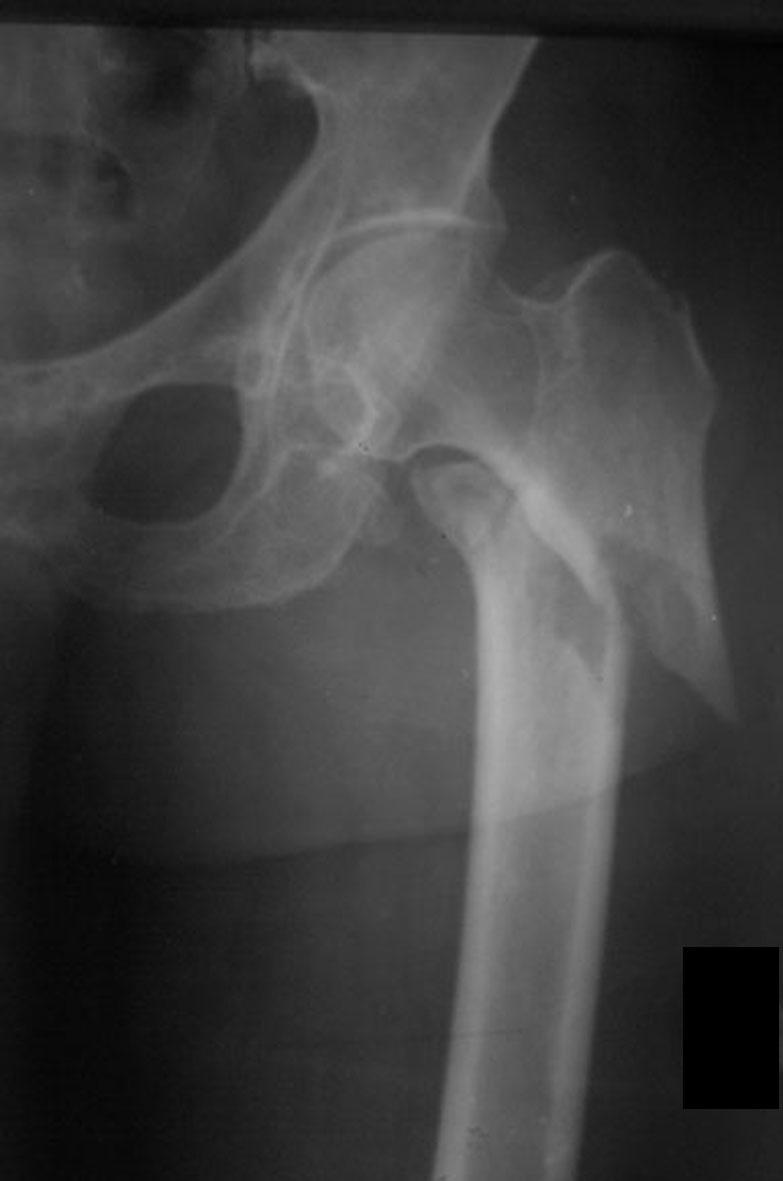

Больной П., 81 года, со слов родственников и больного, упал со стула. Сразу почувствовал резкую боль в правом тазобедренном суставе, самостоятельно встать не смог. Больной предъявляет жалобы на боль в области тазобедренного сустава, которая локализуется под пупартовой связкой. Боль усиливается при пальпации.

Из анамнеза выявлено, что больной страдает гипертонической болезнью. Объективно: лежит в постели, правая нижняя конечность ротирована кнаружи. Больной не в состоянии поднять и удержать выпрямленную в коленном суставе ногу. При попытке поднять поврежденную конечность пятка скользит по поверхности кровати (положительный симптом «прилипшей пятки»), нога отечна, несколько укорочена по сравнению с другой.

П

ри

попытке произвести пассивные и активные

движения, а так же при осевой нагрузке

бедра или шейки (поколачивание по пятке

выпрямленной конечности или по области

большого вертела) боль резко усиливается.

Отмечается усиление пульсации бедренной

артерии под пупартовой связкой

(положительный симптом С. С. Гирголава).

Большой вертел находится выше линии

Розер-Нелатона, выявляется нарушение

равнобедренности треугольника Бриана.

АД 180/90 мм. рт. ст., тоны сердца глухие,

экстрасистолия. Со стороны органов

брюшной полости изменений нет.

Рентгенограмма тазобедренного сустава прямая проекция